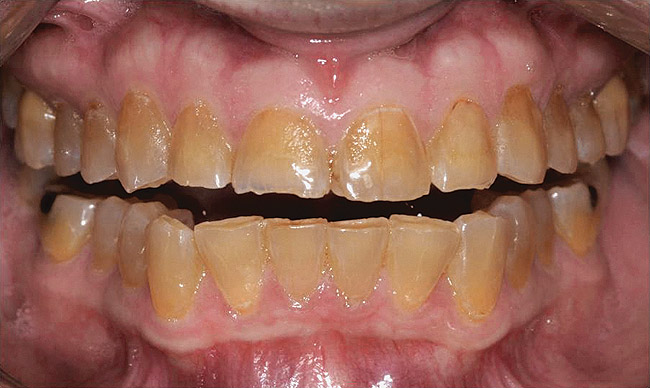

Figure  1  Natural tooth wear.

Figure 1

Figure  5  Loss of tooth surface and yellowing of teeth in a young patient with untreated GERD.

Figure 5